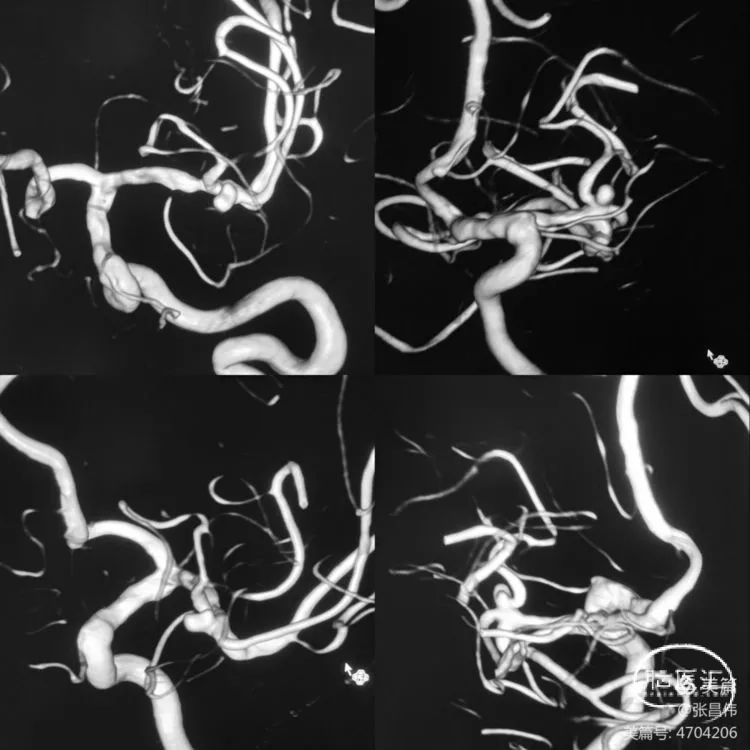

多角度显示动脉瘤,中动脉分三干,瘤体和上干关系密切,宽颈,准备支架!Atlas非常适合这样的血管。

术中操作

直接释放Atlas3.0支架。